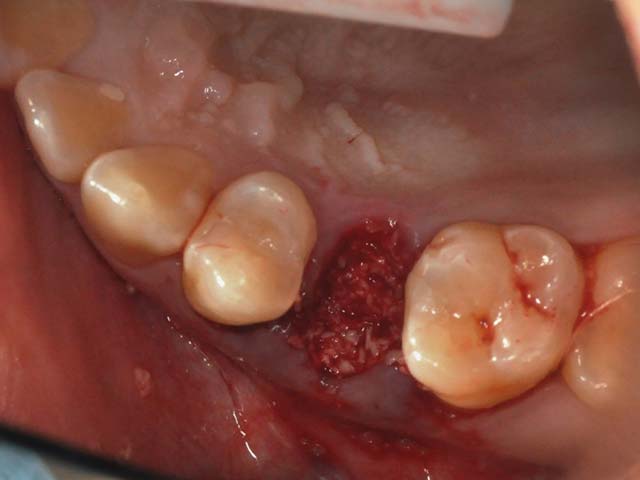

齒槽骨保存術+植牙 首頁 案例分享 人工植牙 齒槽骨保存術+植牙 STEP1拔除掉無法使用的斷裂牙根 STEP2齒槽骨保存術—使用骨粉填補拔牙傷口 術前 V.S 術後 植牙第一階段—植入牙根 植牙第二階段—製作正式假牙